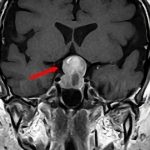

断層撮影

手術前1

手術前2